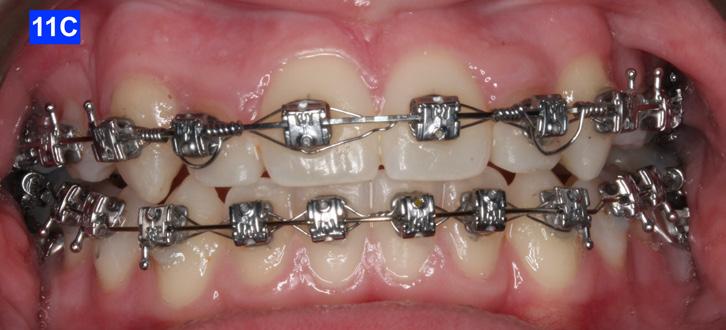

The maxillary cuspids were erupting mesially to the lateral incisors, with very little space to accommodate both teeth without an odontectomy. The expansion was continued (1/4 turn 2x per week), and an attempt was made to create more space for erupting cuspids with an open coil spring (OCS) – between the central incisors and the cuspids (Molar distalization spring, a .010 x .045 - Ortho Organizers). The OCS was measured and cut 4.0 mm longer than the available space. The maxillary arch wire was a .018 SS. An elastomeric chain (EC) was attached from the Hyrax to the lingual button on the lateral incisors. It was necessary to first pull the lateral incisors away from the alveolar process to prevent the break down of the buccal cortical bone around the cuspids (Figure

B, C).

4-A, Figure 3A: The patient transferred to our office, frontal view Figure 3B: The patient transferred to our office, maxilla, occlusal view Figure 3C: The patient transferred to our office, mandible, occlusal view Figure 4A: OCS, frontal view Figure 4B: Hyrax, occlusal view Figure 4C: Retraction of maxillary lateral incisors

The eruption of maxillary cuspids was expedited with the Adrian “U” bend spring5 where the cardinal arch wire was a .016 SS and the secondary arch wire a .014 NiTi5. Since we were working with the PSL brackets, a combination of larger diameter wires would not allow the latch to close (Figure 5–A, B, C). Also note the progress in retraction of the lateral incisors (Figure 5-D).

maxillary first bicuspids was the most advantageous way forward. While the parents were contemplating this recommendation, a closed coil spring was added from the maxillary central incisors to the cuspids and attention was directed towards the lower arch. Treatment of the mandible was begun with leveling arch wires (a .014 NiTi followed by a .018 NiTi). In the author’s experience it is often beneficial to delay treatment in the arch that requires less correction if the opposing is significantly more complex. (Figure 7-A).

When the maxillary teeth were leveled, we placed a .018 SS arch wire and an OCS to create as much space as possible for the lateral incisors. This technique also allowed us to increase the inclination (torque) of the central incisors as they were too retrusive at the start of the treatment (U1/SN 91°). The maxillary lateral incisors were now completely retracted (Figure 6-A, B).

After 18 months of treatment, there was no more space to further distalize the cuspids as they were already touching the first bicuspids. This left inadequate room for the lateral incisors. The posterior sextants could not be distalized as there was only 1.5 mm overbite, and the pt. was severely hyper-divergent (NS/GoM - 40° vs. Norm of 32° +-3). Therefore, the author felt that extraction of the

Finally, after 21 months of treatment, the patient and the parents consented to the odontectomy of the maxillary first bicuspids. The informed consent forms for the extractions and placement of TADs were signed by the parent, and all questions were answered. Risks, benefits, alternatives, and the result of no treatment at all were reviewed. Immediately after the odontectomy of #14(5) and #24(12), 1.6 x 8.0 mm AnchorPro (OrthoOrganizers) TADs were placed just mesially to the maxillary second bicuspids.6 In office power arms (a .018 x.025 SS) were fabricated and bonded to the buccal surface of the maxillary cuspids, just above the bracket.7 The purpose of the power arm is to place the applied force as close to the center of resistance of the tooth as possible. In this manner the line of action (power hook to the TAD) is parallel to the occlusal plane. The source of the force is an EC, and it must be replaced at least bi-weekly. Both arches had a .018 SS arch wire. There was a small off-center bend (tip-back, gable bend) “V” pointing occlusally, mesial to the maxillary second bicuspids.8 The purpose of this bend is to keep the roots parallel during the translation of the cuspids. There was a small OCS between #21(9) and #23(11) to shift the maxillary midline to the right. Another OCS was placed between #32(23) and #34(21) to facilitate the alignment of the mandibular left cuspid (Figure 8-A, B, C, D).